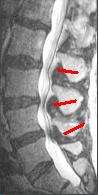

The diagnosis of spinal stenosis involves a complete evaluation of the spine. The process usually begins with a medical history and physical examination. X-ray and MRI scans are typically used to determine the extent and location of the nerve compression.

MRI

The MRI has become the most frequently used study to diagnose spinal stenosis. The MRI uses electromagnetic signals to produce images of the spine. MRIs are helpful because they show more structures, including nerves, muscles, and ligaments, than seen on x-rays or CT scans. MRIs are helpful at showing exactly what is causing spinal nerve compression.[15]